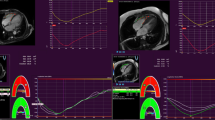

Analysis of RV strain data revealed lower value of RV-St apex, and RV-GLS in DCM patients compared to normal subjects (Fig. 1), while RV-St base did not significantly differ in the two groups (Table 3). RV-St apex was higher than RV-St base in normal subjects (p < 0.0001), but lower than RV-St base in the DCM group (p = 0.002) (Fig. 2).

A & B: RV-GLS in a dilated cardiomyopathy patient (A), and in a normal subject (B). Six strain curves are shown in each case representing basal, mid and apical segments of both RV free wall and interventricular septum. The value of right ventricular global longitudinal strain was 15.9% in the dilated cardiomyopathy patient and 24% in the normal subject